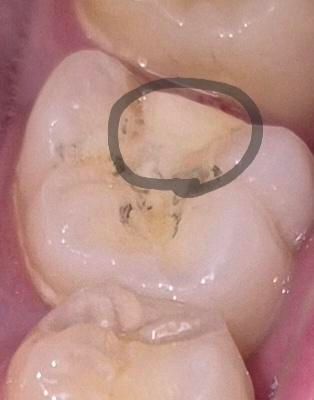

동그라미 친 부분은 제 치아인가요?.

금인레이가 떨어진 치아인데 동그라미 친 부분은 제 치아인가요? 아니면 다른 물질인가요?

그리고 저 검은색은 충치인가요? 아니면 금인레이 붙일때 사용된 풀인가요?

동그라미 친 부분의 하얀색은 인레이치료를 할 당시에 충치를 파내고 울퉁불퉁해진 구멍을 인레이가 들어갈 수 있게 매끈하게 메꾸기 위해 사용한 충전재료입니다.

주변의 검정색은 충치는 아닌 것으로 보이고, 인레이 테두리쪽부터 생긴 틈사이로 변색이 된 것 같습니다.

금 인레이 하방에 깔아둔 기저재 같습니다 즉, 치아는 아니고 수복물로 보입니다

검은건 충치보단 얼룩같습니다